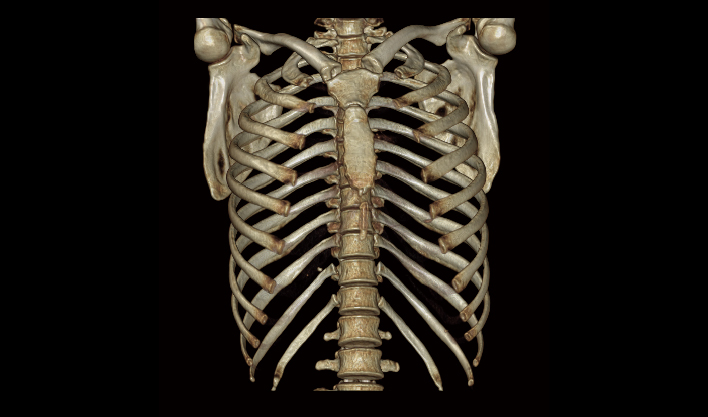

El detector de área amplia, combinado con la rotación de alta velocidad, garantiza imágenes de alta resolución y minimiza los artefactos de movimiento.

El detector de cuerpo ancho de cuarta generación, de desarrollo propio, cubre más áreas de tejido.

La matriz de reconstrucción de 1024*1024 amplía los datos de la imagen cuatro veces. Combinado con imágenes de corte fina, incluso las lesiones más invisibles son claramente visibles.